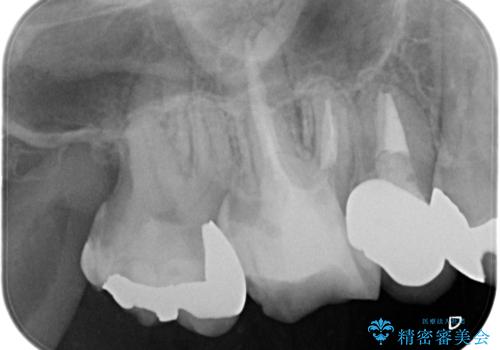

- 定期検診にて虫歯を見つけ、メタルボンドクラウンにて修復補綴治療を行なっております。

歯肉縁下まで虫歯が進行していたため歯周外科を併用して治療を行なっております。